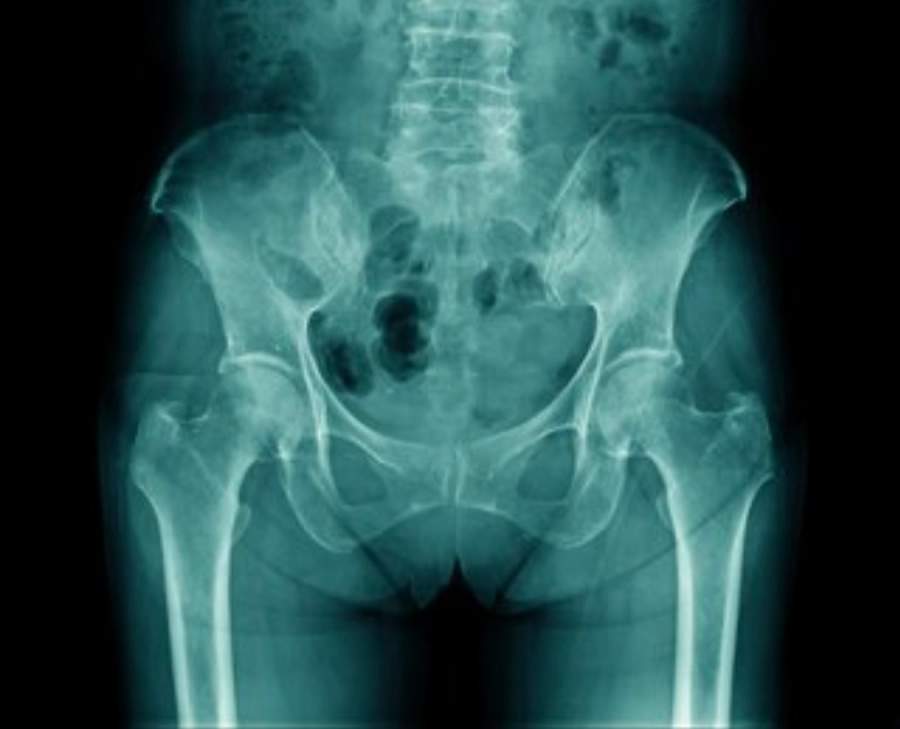

Pessoas com mais de 60 anos têm mais probabilidade de sofrer quedas e por isso estão mais propensas a sofrer fratura de fêmur ou de quadril. “As estatísticas mostram que um terço da população masculina e metade da população feminina vai ter uma fratura por osteoporose durante a vida”, alerta o médico Christiano Saliba Uliana, ortopedista do Hospital VITA, especialista em cirurgia do quadril e traumatologia.

O Dr. Saliba explica que com o envelhecimento, o esqueleto vai perdendo a capacidade de reter cálcio, e fica menos denso, mais ‘poroso’, e assim, mais vulnerável a sofrer fraturas. As fraturas do quadril são hoje responsáveis por grande parte dos internamentos e procedimentos cirúrgicos na área da Ortopedia. Segundo o ortopedista, milhões de pessoas são vítimas desse tipo de fratura, que além de causar muitas limitações físicas ao indivíduo, resulta em um alto índice de mortalidade.